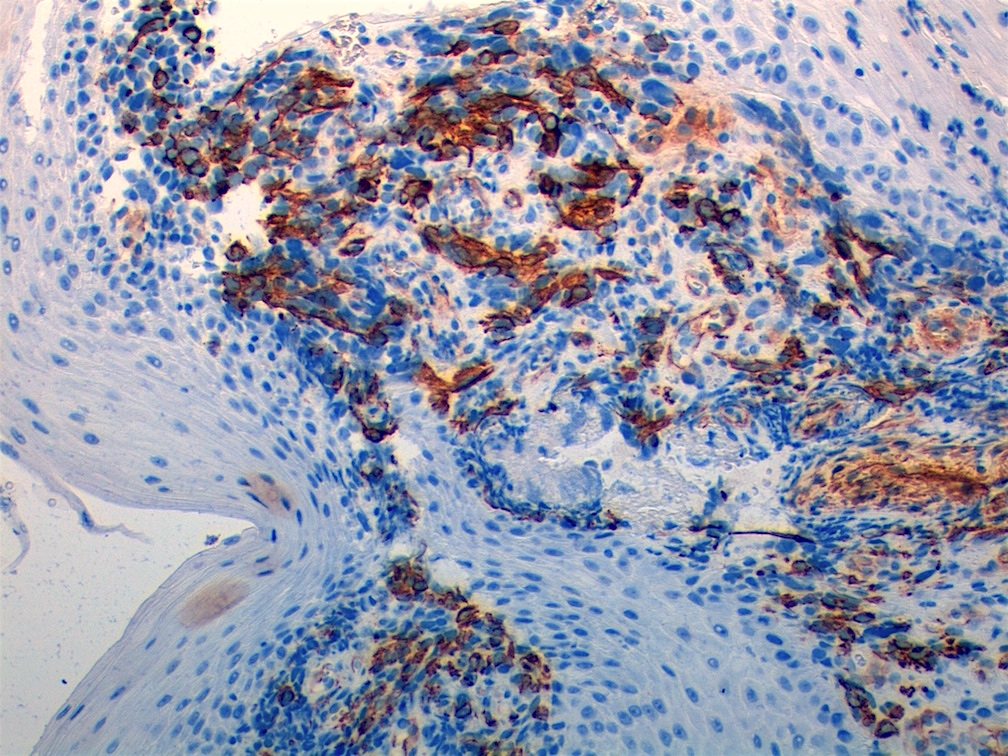

Microscopic (histologic) images

Contributed by Erdener Özer, M.D., Ph.D. and Mark R. Wick, M.D.

Contributed by Carolina Martinez Ciarpaglini, M.D., Ph.D. (Case #276) - tonsillar mass

AFIP images - anaplastic rhabdomyosarcoma

AFIP images - botryoid variant

Positive stains

- Desmin, MyoD1 or myogenin are critical to document (Pathol Oncol Res 2008;14:233)

- Without myogenic differentiation (MyoD1 or myogenin), it is very difficult to diagnose embryonal rhabdomyosarcoma

- These stains will be less diffuse than in alveolar rhabdomyosarcoma and can be extremely focal

- Botryoid variant: Desmin, MyoD1, smooth muscle actin, muscle specific actin (Pediatr Dev Pathol 2005;8:427)